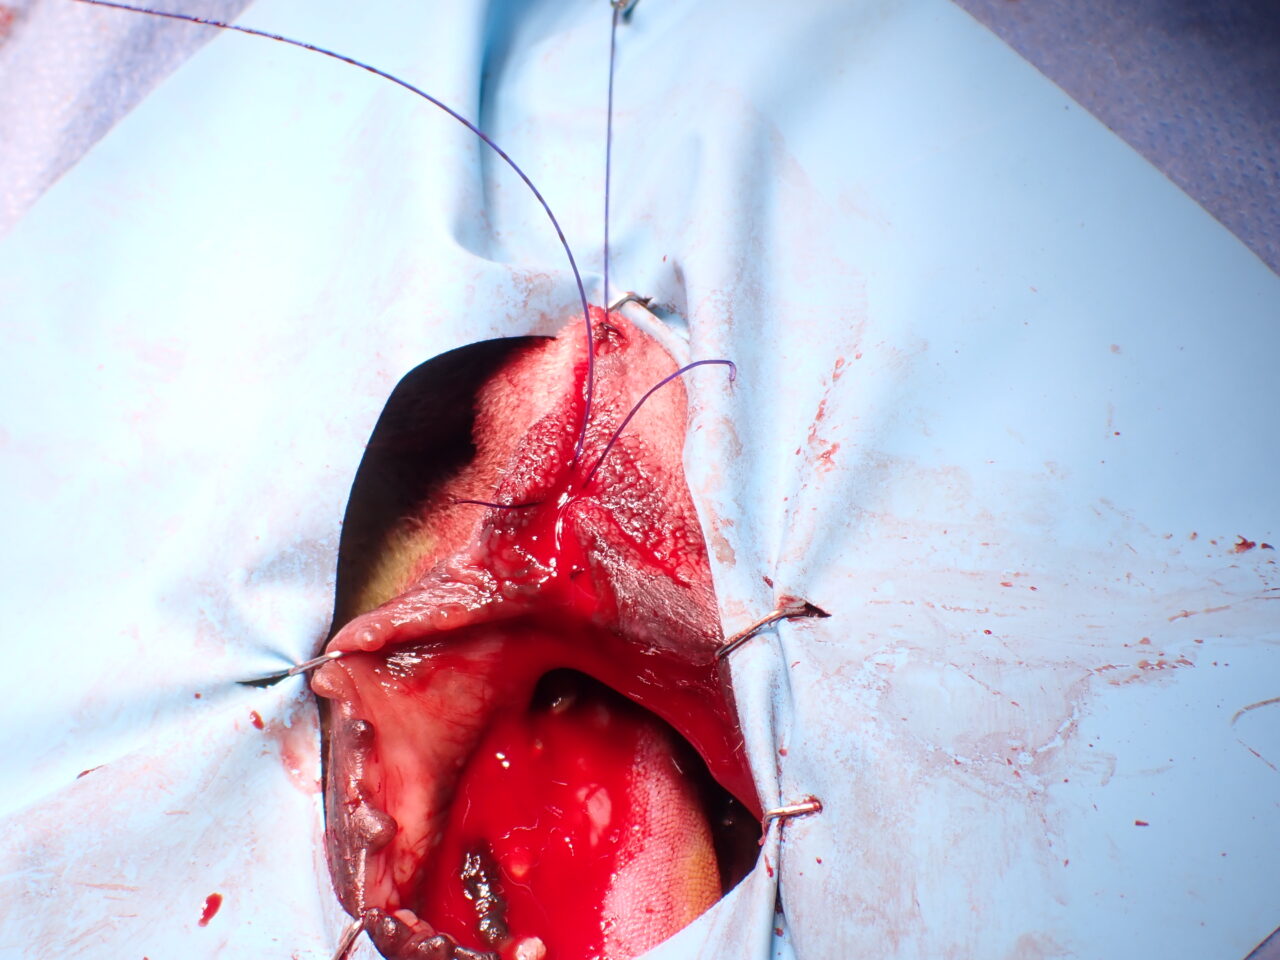

口唇部メラノーマ Wedge Resection Technique

口唇部のWedge Resection Technique

- Wedge Resection Techniqueを使用して口唇の欠損を再建。

- 口唇欠損部に縫合